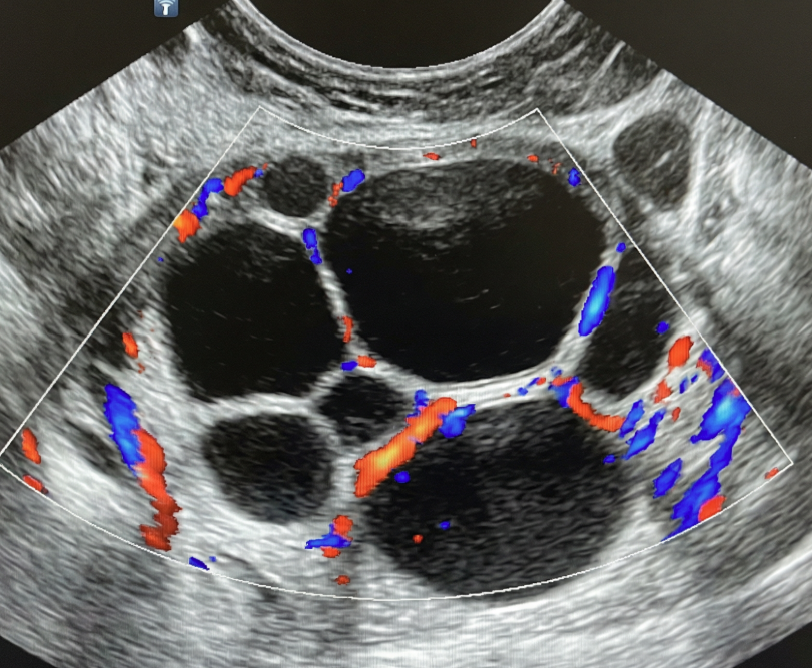

Risco: ≥50%Cisto unilocular com ≥ 4 projeções papilares, cisto multilocular com componente sólido e IC = 3–4, lesão sólida com IC = 4 ou superfície irregular, presença de ascite e/ou nódulos peritoneais.

Achados ultrassonográficos

Conduta

Acompanhamento pelo gineco-oncologista